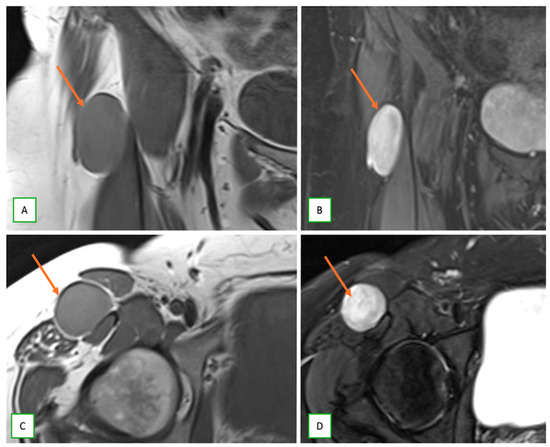

- Primary Sarcomas: Soft-tissue sarcomas are uncommon, accounting for just over 1% of adult malignancies. Synovial sarcoma, clear cell sarcoma, and epithelioid sarcomas are known to involve peripheral nerves. CT/MR reveals a large soft tissue mass with areas of necrosis or calcification and heterogeneous contrast enhancement. F-18 FDG uptake is useful for both tumor staging and treatment assessment (Figure 26, Figure 27 and Figure 28).